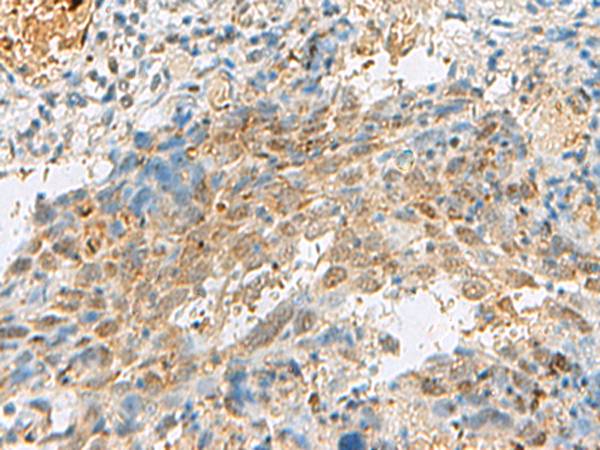

The image is immunohistochemistry of paraffin-embedded Human cervical cancer tissue using (PRPF3 Antibody) at dilution 1/30. (Original magnification: ×200)